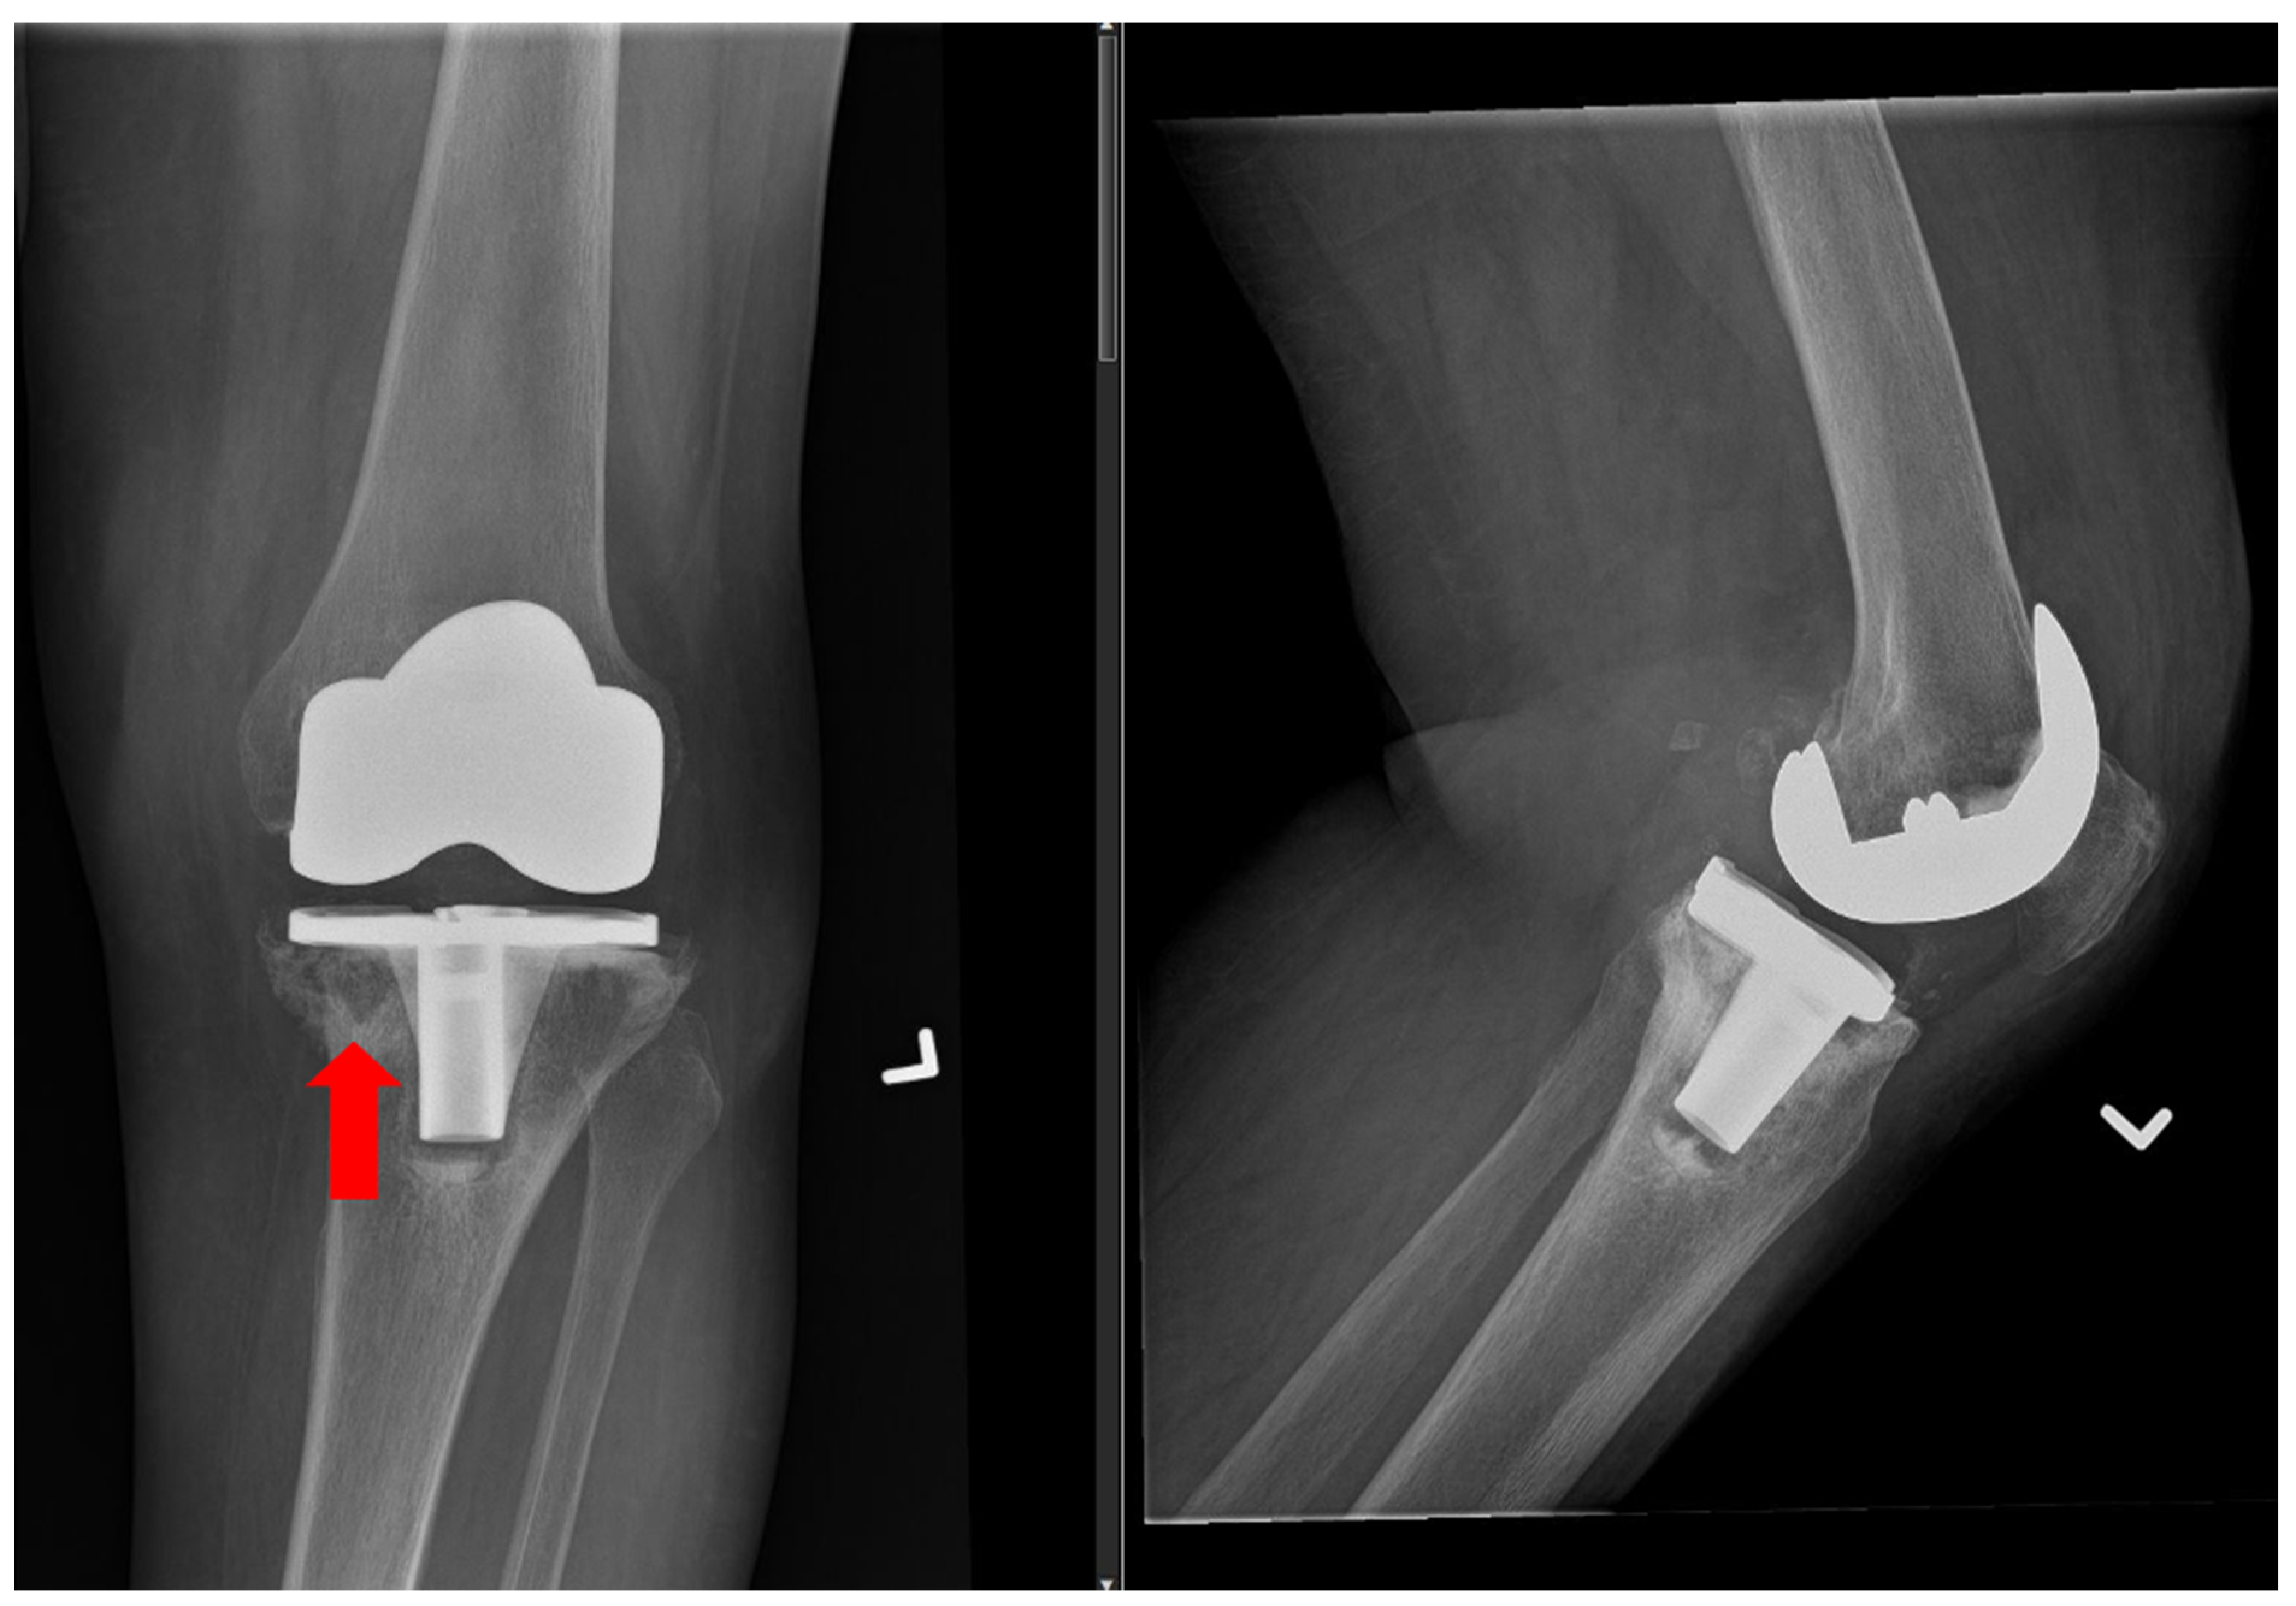

- Saleh, K.J.; Thongtrangan, I.; Schwarz, E.M. Osteolysis: Medical and surgical approaches. Clin. Orthop. Relat. Res. 2004, 427, 138–147. [Google Scholar] [CrossRef]

- Abu-Amer, Y.; Darwech, I.; Clohisy, J.C. Aseptic loosening of total joint replacements: Mechanisms underlying osteolysis and potential therapies. Arthritis Res. Ther. 2007, 9 (Suppl. S1), S6. [Google Scholar] [CrossRef]

- Bozic, K.J.; Kamath, A.F.; Ong, K.; Lau, E.; Kurtz, S.; Chan, V.; Vail, T.P.; Rubash, H.; Berry, D.J. Comparative Epidemiology of Revision Arthroplasty: Failed THA Poses Greater Clinical and Economic Burdens Than Failed TKA. Clin. Orthop. Relat. Res. 2015, 473, 2131–2138. [Google Scholar] [CrossRef]